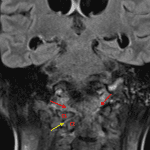

- Heterogenous T1/T2 signal in the clivus, occipital condyles, and C1 and C2 vertebral bodies with patchy enhancement and osseous erosions

- Circumferential epidural enhancement from the skull base through C2 with mild pial enhancement along the surface of the brainstem

- Fluid signal and enhancement in the bilateral atlantooccipital and right atlantoaxial joints

- Right lateral subluxation of the C1 on C2 with the odontoid process indenting the left ventral aspect of the thecal sac

- Material layering in the occipital horns of the lateral ventricles and in the fourth ventricle which restricts diffusion and is T2 hypointense relative to CSF

- Diffuse ventriculomegaly with periventricular T2/FLAIR hyperintensity

- Hypoenhancement and abnormal flow-related signal loss in the left transverse and sigmoid sinuses extending into the left internal jugular vein

Findings concerning for skull base osteomyelitis involving the clivus, occipital condyles, and C1 and C2 vertebral bodies complicated by meningitis, ventriculitis, and thrombosis of the left transverse and sigmoid sinuses and left internal jugular vein. Cervical spine MRI with and without contrast is recommended for further assessment.

Fluid signal and enhancement in the bilateral atlantooccipital and right atlantoaxial joints concerning for septic arthritis. As a likely complication of this infectious process, there is right lateral subluxation of the C1 on C2 with the odontoid process indenting the left ventral aspect of the thecal sac, concerning for instability.